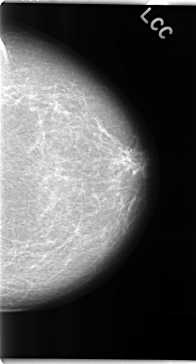

C_0156_1.LEFT_CC

LEFT_CC LINES 4728 PIXELS_PER_LINE 2544 BITS_PER_PIXEL 12 RESOLUTION 50 NON_OVERLAY